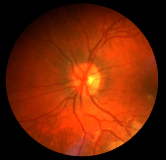

Background and Objective: The condition of vessel of the human eye is an important factor for the diagnosis of ophthalmological diseases. Vessel segmentation in fundus images is a challenging task due to complex vessel structure, the presence of similar structures such as microaneurysms and hemorrhages, micro-vessel with only one to several pixels wide, and requirements for finer results.

Ophthalmologic diseases, including age-related fovea degeneration, diabetic retinopathy, glaucoma, hypertension, arteriosclerosis and choroidal neovascularization, are the main causes for blindness. Thus, early diagnosis and treatment of these diseases are critical for reducing the risk of blindness [1]. As an important component in retinal fundus images, vessel condition is always used as an indicator by ophthalmologists for diagnosing various ophthalmologic diseases. Since manual annotation of blood vessels in retinal images is tedious and time-consuming and requires experience in clinical practice, automated vessel segmentation is urgent [2].

Automated segmentation of retinal blood vessels has attracted significant attention over recent decades [3]. However, vessel segmentation is a challenging task for computers due to the following reasons [4]. 1) The structure of retinal vessels is complex, and there are huge differences between vessels in different local areas in terms of size, shape and intensity. The first challenge is to build a model that can describe the complex vessel structure. 2) Some structures such as striped hemorrhage have similar shape and intensity with vessels. Furthermore, a micro-vessel is thin, whose width usually ranges from one to several pixels, making it easy to be confused with noises. The second challenge is to distinguish vessels from other similar structures or noises. 3) Compared to other object segmentation tasks such as Pascal VOC [5], vessel segmentation requires finer results to keep the structure of different vessels for subsequent vessel based diagnosis. The third challenge is to refine vessel pixels so that the structure of vessels can be well kept.

The DRIVE [29] dataset consists of 40 color fundus photographs with a resolution 565584. The dataset has been divided into a training set and a test set, each containing 20 images. For training images, a single manual segmentation of the vasculature is available. For test cases, two manual segmentations are available. One is used as the gold standard, and the other one can be used to compare computer generated segmentations with those by an independent human observer. For each image in DRIVE, a binary mask for FOV (Field of View) area is provided. To select the best epoch, we divide training set into training set and validation set. We use the first 15 images for training and the rest 5 images for validation.

The STARE [30] dataset consists of 20 fundus images with a resolution 700605. Each image has pixel-level vessel annotation provided by two experts. The annotations by the first expert are used as ground truth. In addition, this dataset does not provide partition of training set and testing set. Therefore, we used the same data partitioning method as in literatures [18, 16, 31] (10 images for training and the rest 10 images for testing). Note that the same method of data partitioning is used in all the comparison methods in the paper. We select the first 7 images for training and the rest 3 images for validation.

The CHASE_DB1 [3] dataset contains 28 retinal images with a resolution 999960. The images are collected from both the left and right eyes of 14 people. Since the partition of training set and testing set is not present, we divided this dataset into 2 sets according to [19, 23, 24, 32, 33], where the first 20 images are considered as training set and the rest 8 images are considered as testing set. Note that the same method of data partitioning is used in all the comparison methods in the paper. In addition, due to the high resolution of retinal images in this dataset and limited GPU memory, the images are first scale to a much lower resolution so that it is possible to fed them into GPU memory. We divide the training set into two parts as well in this dataset. We select the first 15 images for training and the rest 5 images for validation.